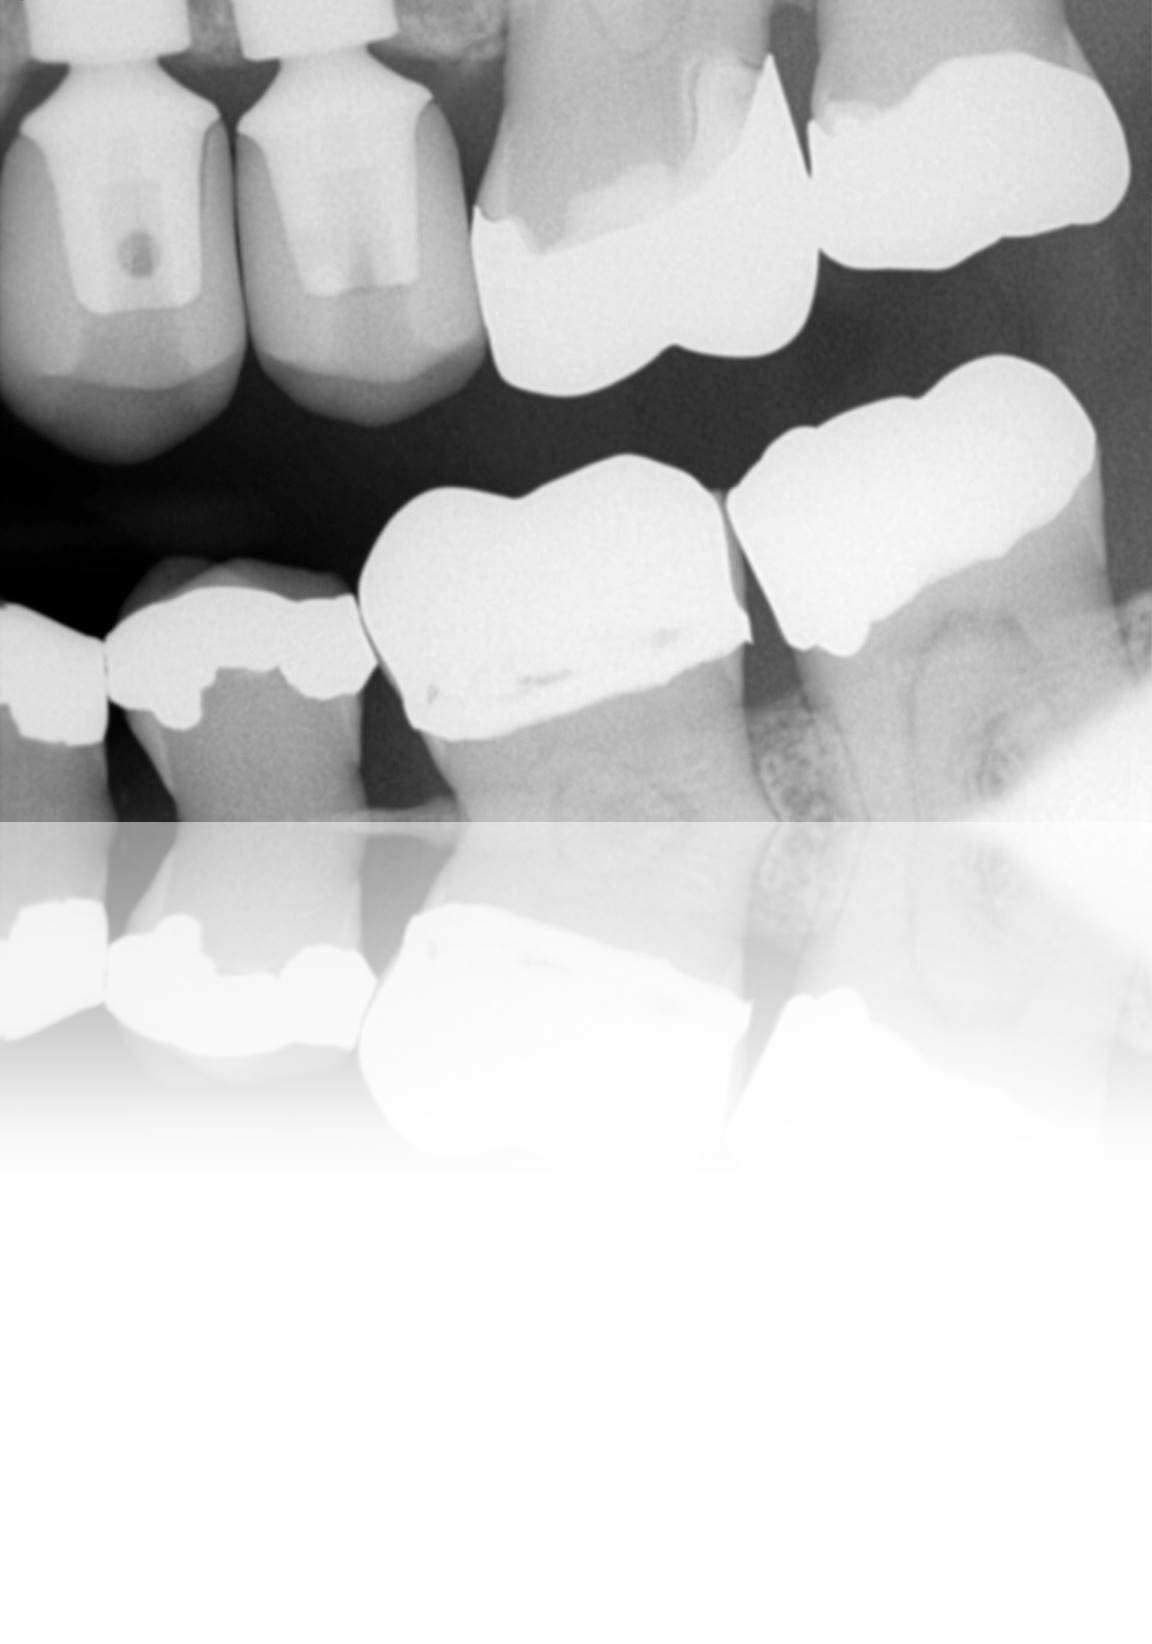

Figure 1. Preoperative occlusal view of a 35-year-old man missing his second premolar, which would be replaced with an implant and screw-retained abutment/restoration.

Figure 1

Figure 2. Preoperative radiograph suggests a straightforward implant placement case, with ample space and sufficient bone for positioning the implant.

Figure 2